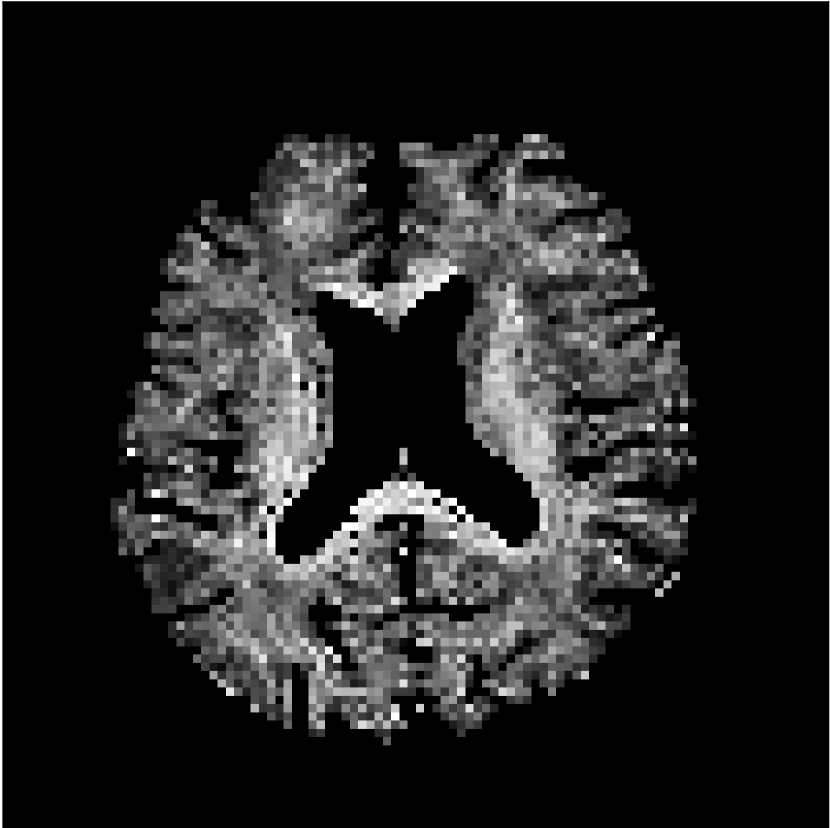

Figure 8 shows examples of non-diffusion-weighted images before and after processing. The raw images (Raw) served as the input for the magnitude deep learning (MCNN) and complex deep learning (CCNN) methods.

Raw

MCNN,

MCNN Resid.,

CCNN,

CCNN Resid.,

No PF

5/8 PF

Both methods remove artifacts, but the MCNN method allows residual rippling artifacts to pass through in the presence of partial Fourier. These rippling artifacts are not present in the CCNN method.